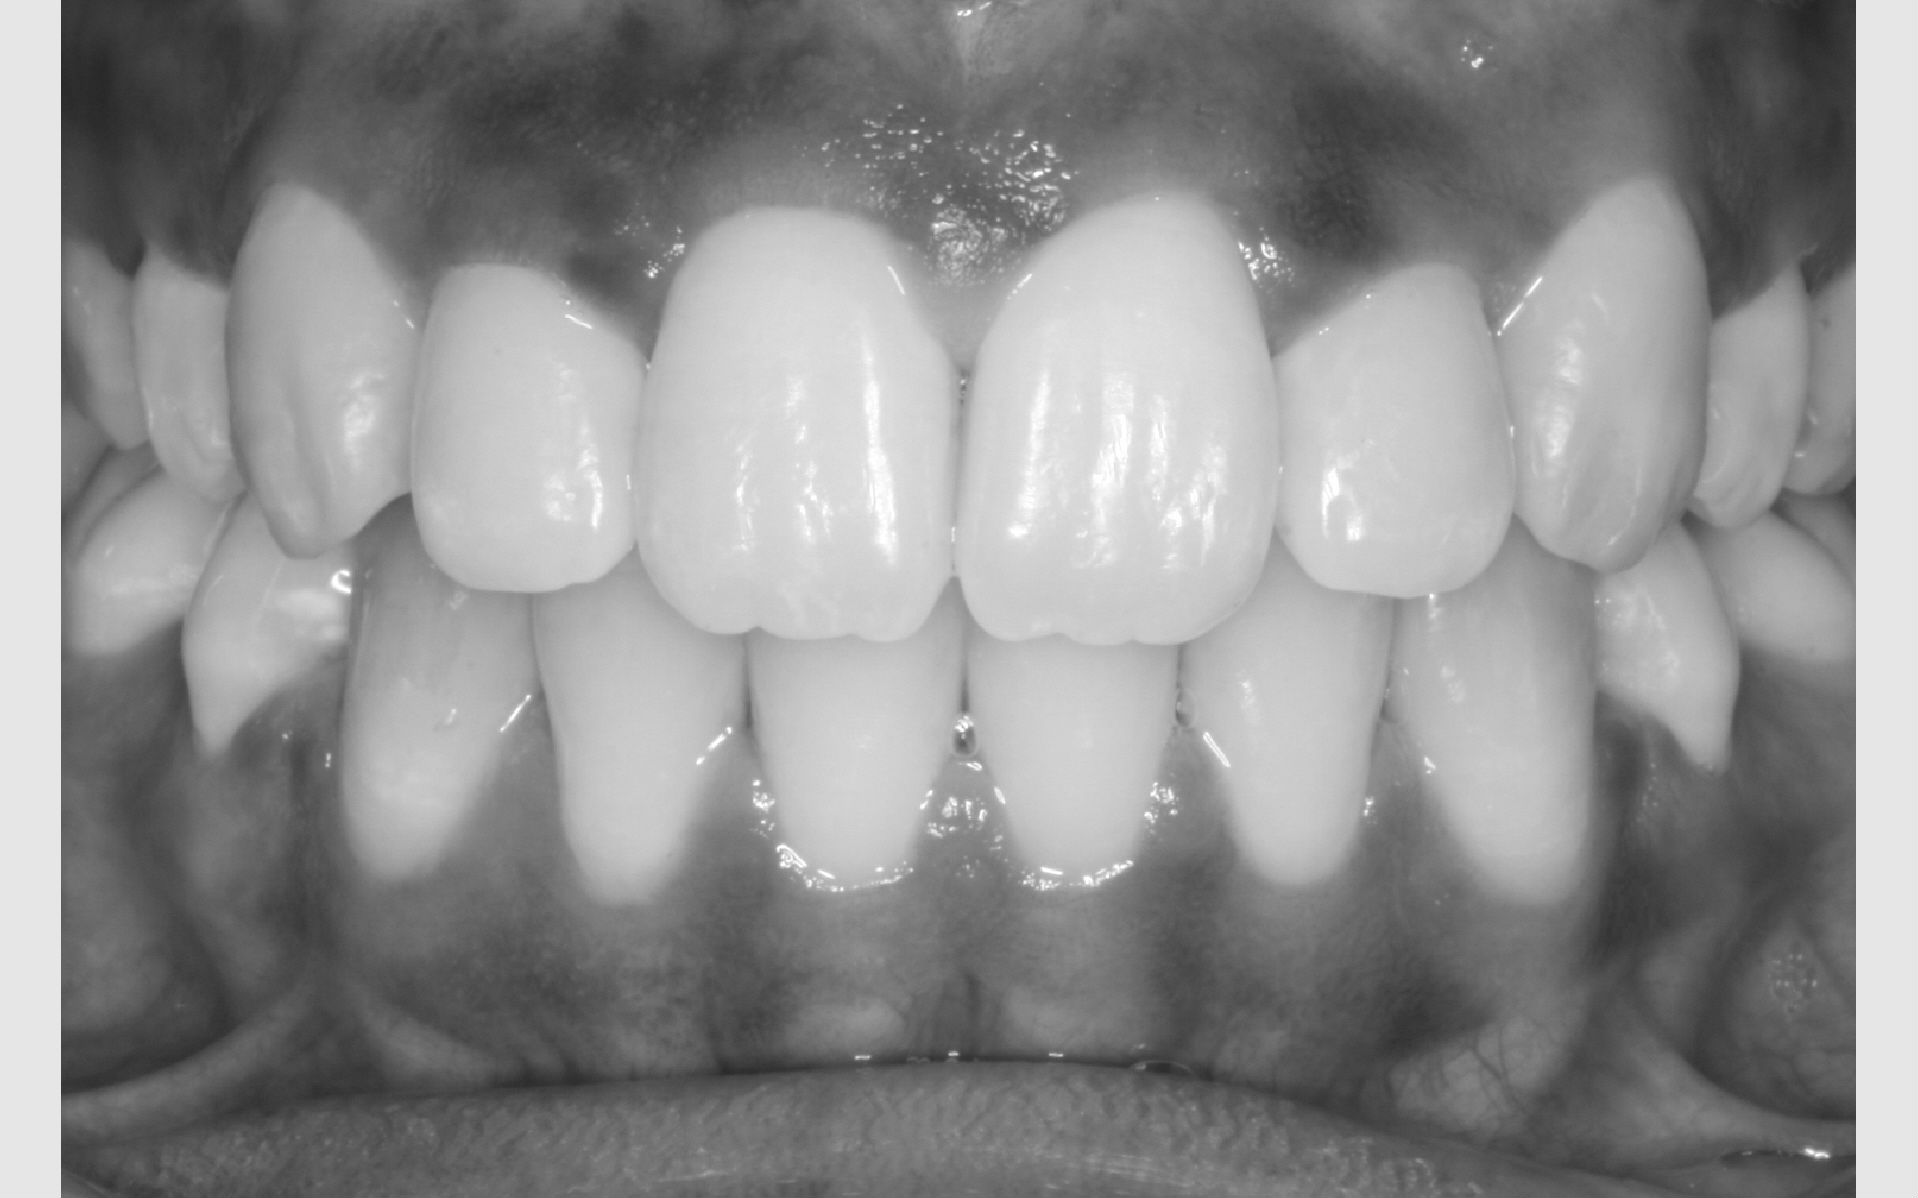

Første gang dit barn besøger Tandreguleringsklinikken, bliver der lavet studiemateriale.

Studiemateriale, består af modeller, fotos og røntgenbilleder af tænder og ansigt. Der bliver også udleveret et helbredsskema, som skal udfyldes på stedet. Det er vigtigt at vide, om jeres barn er sundt og raskt, eller om der er særlige hensyn, vi skal tage - eksempelvis til medicin med videre.

Der bliver taget billeder "udenpå og indeni" samt røntgenbilleder.

Dit barn skal selv holde sine læber til side med en læbeholder, mens tænderne bliver fotograferet. Billederne har følgende formål:

Anden gang dit barn kommer på Tandreguleringsklinikken, er det for at snakke med den specialtandlæge, der har lavet den gældende behandlingsplan. Specialtandlægen forklarer, hvad problemet drejer sig om, og med hvilken bøjle dit barn kan få rettet tænderne.

Der informeres om, hvilke risici der er forbundet med at få tænderne rettet, og hvilke der eventuelt er ved at lade være. I får også at vide, hvor lang tid behandlingen formentlig tager, og hvilke bøjler dit barn efterfølgende skal have for at holde tænderne på plads.